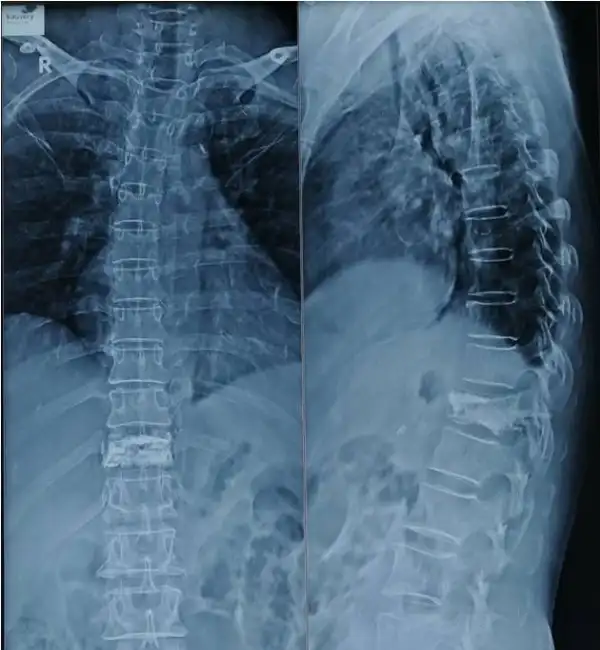

Multi level fracture Pre Op X ray

Multilevel vertebroplasty Post Op x ray